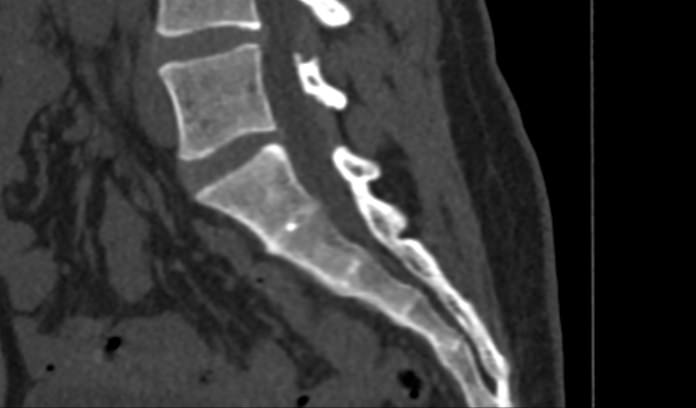

Мультиспиральная компьютерная томография – это современный наиболее достоверный метод диагностики различной патологии крестцово-копчикового сочленения, основанный на послойном сканировании органов и тканей с использованием рентгеновских лучей. Благодаря получаемым тонким срезам с шагом от 0,5 мм и последующей обработке данных компьютерными программами удается получить изображения костных структур, связочного аппарата, межпозвоночных дисков и окружающих тканей. В дальнейшем данные могут быть преобразованы в 3D-изображения исследуемой анатомической области. Это позволяет выявлять различные заболевания позвоночника на ранних стадиях и назначать своевременное лечение.

КТ крестцово-копчиковой области может выявить наличие следующих патологий:

- вывихи в крестцово-копчиковом сочленении;

- остеохондроз;

- септическую, туберкулезную или метастатическую деструкцию крестца;

- остеопороз (визуальная оценка);

- Смещение или перелом позвонков, а также оценить локализацию отломков позвонков;

- гематомы в области поврежденной области;

- воспалительные процессы;

- новообразования и метастазы;

- последствия травм и операций;

- дегенеративно-дистрофические изменения.